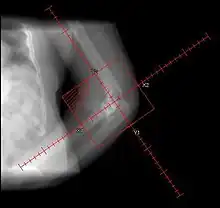

During the early stage, an x-ray will not be helpful because there is no calcium in the matrix. (In an acute episode which is not treated, it will be 3– 4 weeks after onset before the x-ray is positive.) Early laboratory tests are not very helpful. Alkaline phosphatase will be elevated at some point, but initially may be only slightly elevated, rising later to a high value for a short time. Unless weekly tests are done, this peak value may not be detected. It is not useful in patients who have had fractures or spine fusion recently, as they will cause elevations.

The only definitive diagnostic test in the early acute stage is a bone scan, which will show heterotopic ossification 7 – 10 days earlier than an x-ray. The three-phase bone scan may be the most sensitive method of detecting early heterotopic bone formation. However, an abnormality detected in the early phase may not progress to the formation of heterotopic bone. Another finding, often misinterpreted as early heterotopic bone formation, is an increased (early) uptake around the knees or the ankles in a patient with a very recent spinal cord injury. It is not clear exactly what this means, because these patients do not develop heterotopic bone formation. It has been hypothesized that this may be related to the autonomic nervous system and its control over circulation.[3]